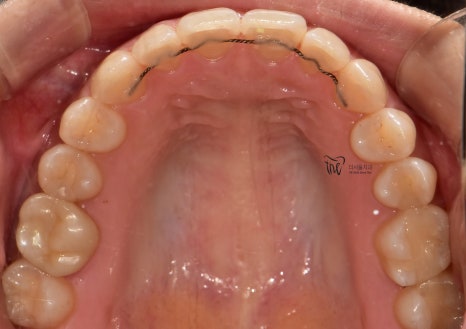

그러면서 치아의 중심선이 맞지 않으면서

악궁의 크기 또한 비대칭인것을 볼 수 있네요.

올려드린 5개의 중첩사진을 보면,

단순히 압하로 끝날 문제가 아니라는 것을

볼 수 있으면서 클린첵 시뮬레이션에 따라서

치열 및 악궁의 확장에 따른,

그리고 이가 맞물리는 포인트의 위치 변경에

따라서 과개교합 증세가 개선이 되는 것을

한 눈에 볼 수 있습니다.